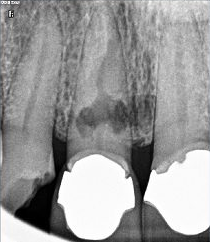

1. What is the condition in the distal surface of the tooth # 4.6?

2. What is the condition in the distal surface of the tooth # 4.7?